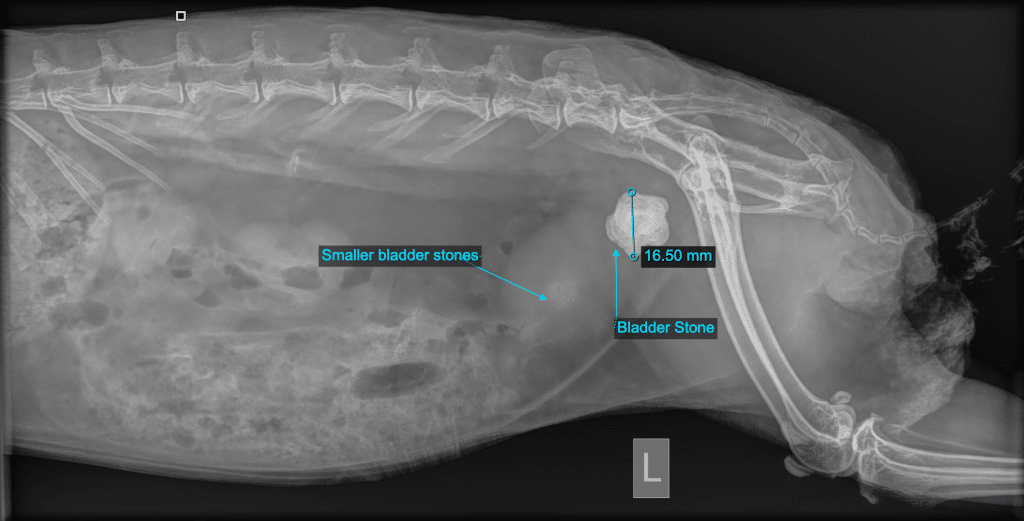

Bladder problems are very common in rabbits, and for the most part problems with urination can be due to infection or thickening of the urine to form a sand-like sludge. However, Obi’s x-rays showed he has been keeping a big secret for quite some time.

Obi’s X-Ray with Annotations

Within Obi’s teeny little rabbit bladder was a massive 1.5cm rock! The bladder stone was so big, that looking at the x-ray, you could almost miss the numerous little stones behind it.